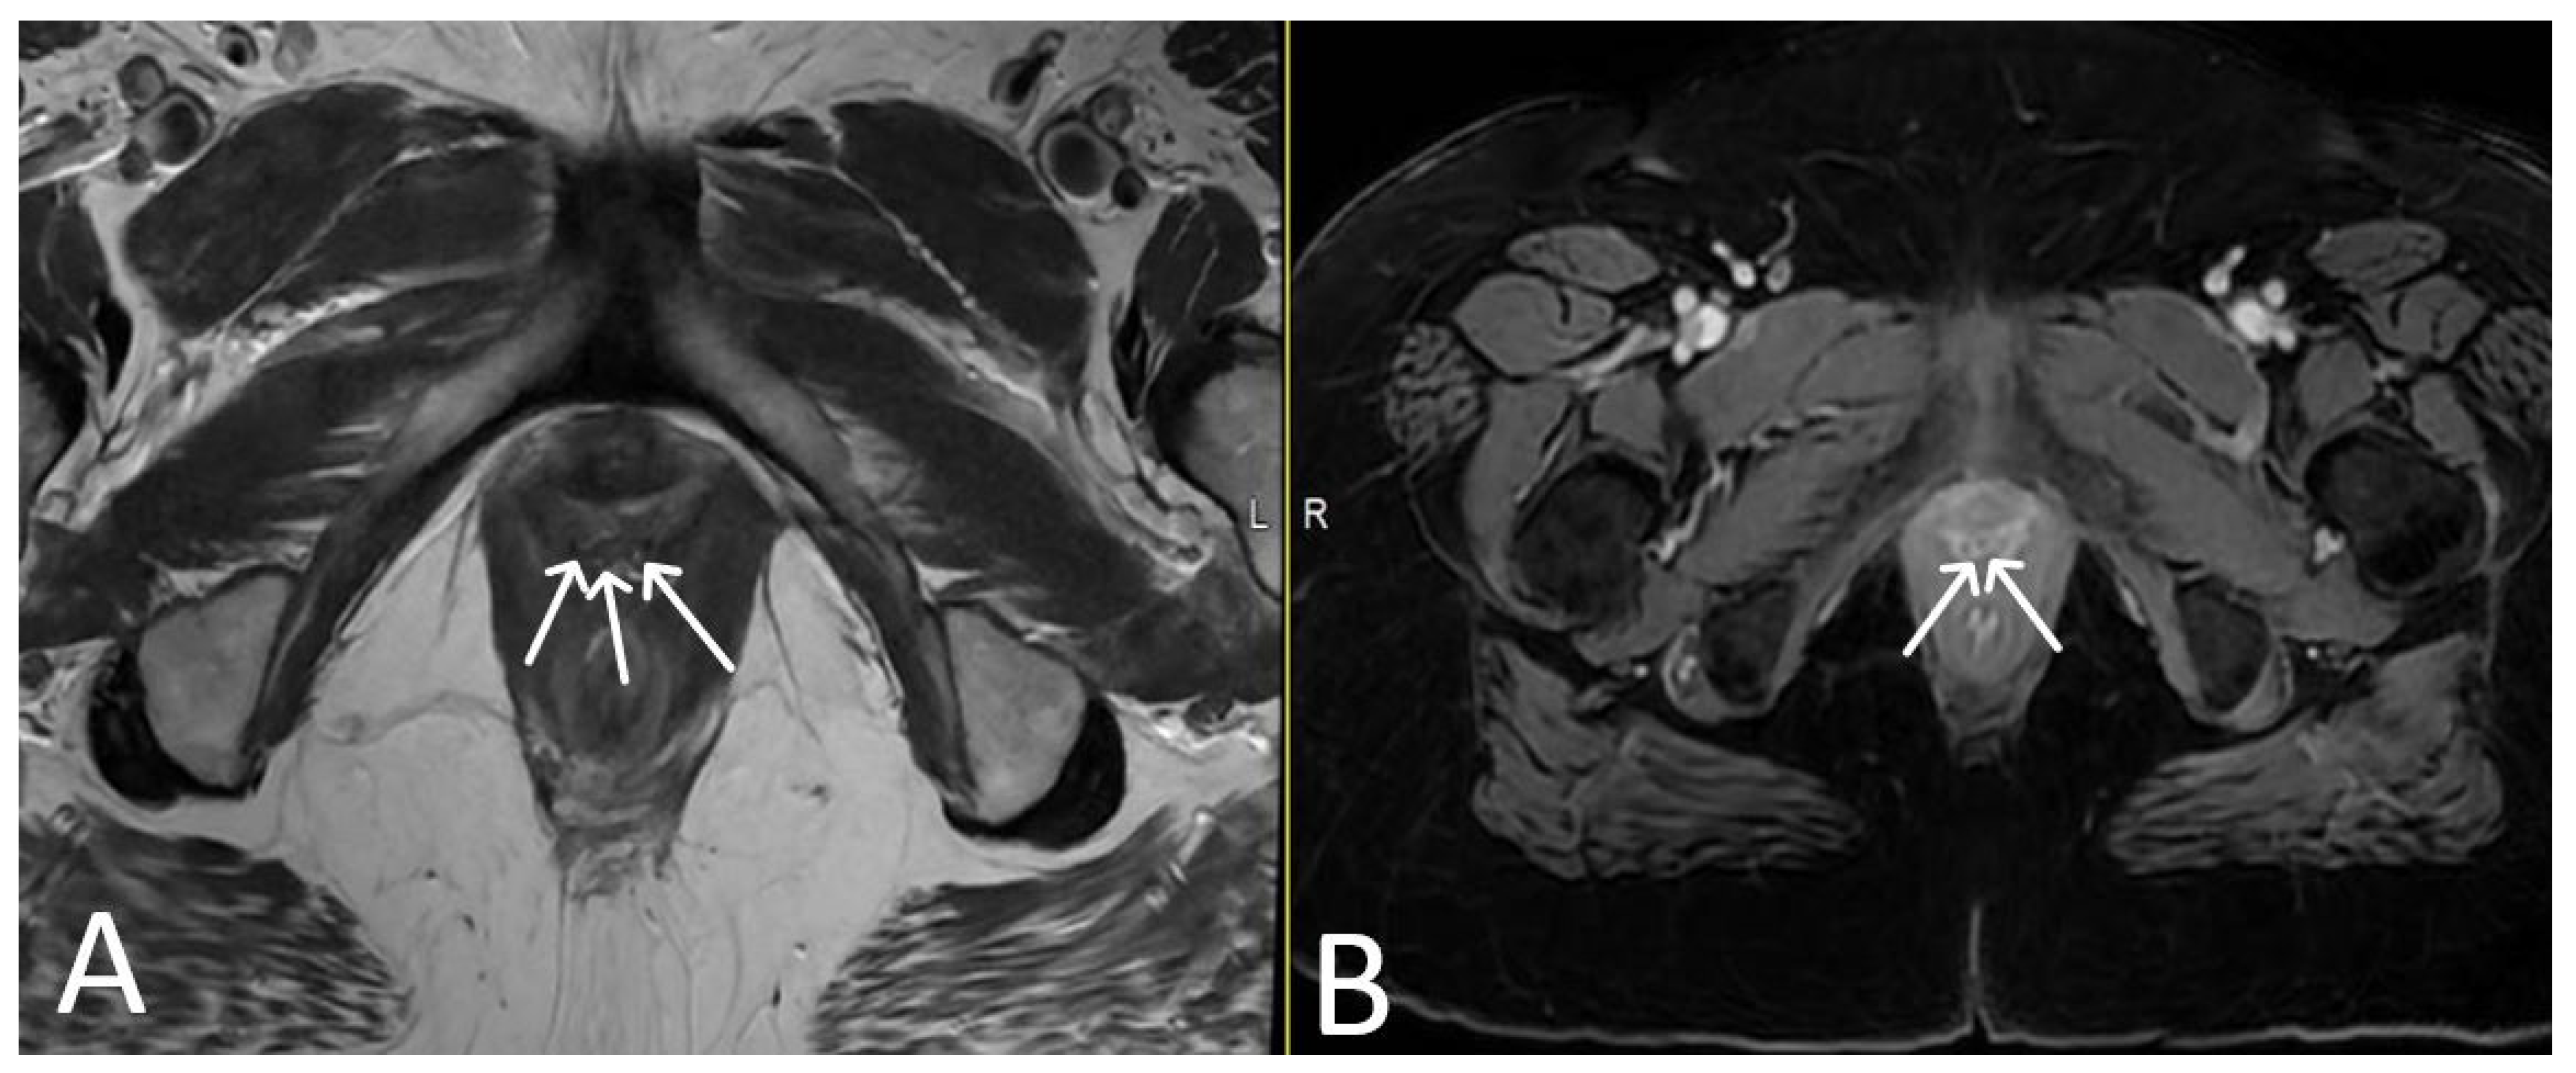

5. Urethral Mesh Complications

5.1. Short-Term Complications

5.2. Long-Term Complications